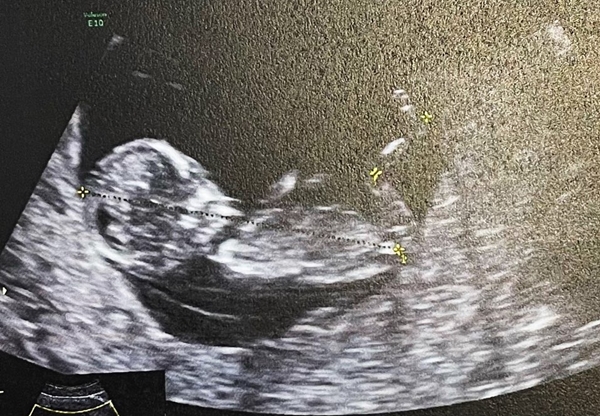

ขอแสดงความยินดีกับคุณแม่ป้ายแดง "น้ำชา ชีรณัฐ" โดยเจ้าตัวโพสต์ภาพประกาศข่าวดี เป็นภาพตนเองและสามี กับรูปอัลตราซาวน์ลูกน้อย ในมือของว่าที่คุณแม่ กับุข้อความว่า "Our+1" ท่ามกลางความยินดีของเหล่าคนในวงการบันเทิง และแฟนคลับเป็นจำนวนมาก....

ล่าสุด ว่าที่คุณแม่ น้ำชา ได้เผย ว่า "ตื่นเต้นมาก เป็นอีกหนึ่งสเต็ปของชีวิต ก็ต้องทำให้ดีที่สุด เห็นเค้าในท้องครั้งแรก รู้สึกตื้นตันมาก หาหนังสือมาอ่าน ถามคนที่มีประสบการณ์ ตอนนี้อายุครรภ์ 4 เดือนแล้ว ไม่มีอาการแพ้ใดๆ เลย แค่ทานไม่ได้เยอะมาก ตอนนี้ทราบเพศลูก แต่ขออุบไว้ก่อน รอพร้อมแล้วจะแจ้งอีกที"